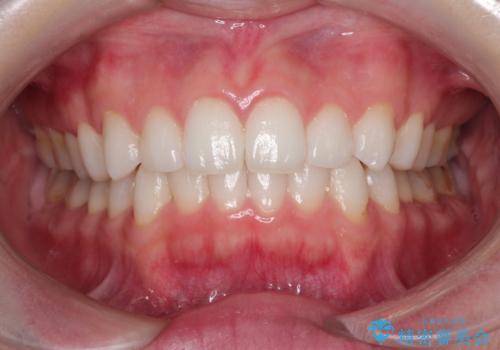

使用時間を守っていただけたので、スムーズに治療を終わることができました。

1周目が終わり、かなり綺麗になりましたがもう少し納得出来るまで続けたいという要望に答えてくださり、今2周目を終え本当に満足いく結果になりました。ありがとうございます。矯正を通して歯は意外と簡単に動くのだなと身をもって感じたのでこれからもリテーナーを怠らずつけ続けたいと思います。